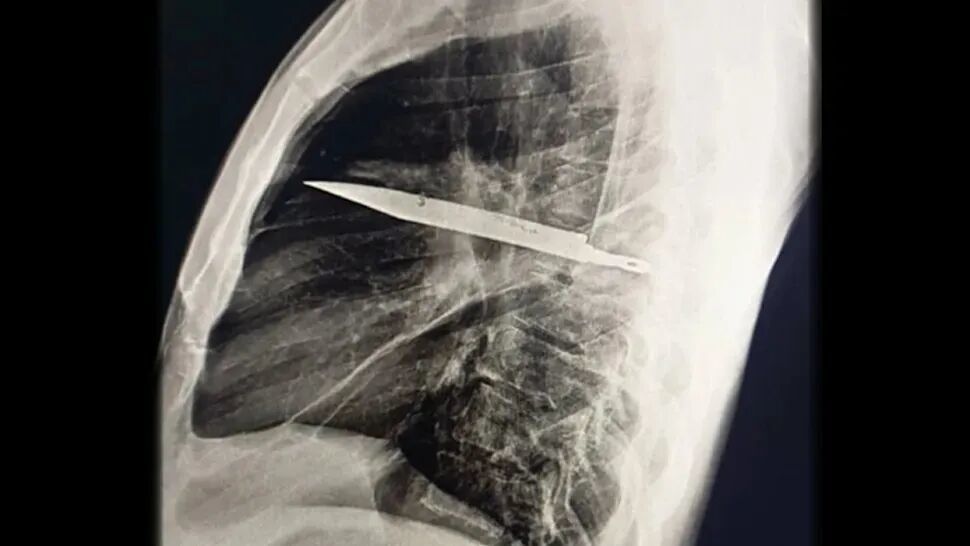

一位44岁的坦桑尼亚男子成了今年最令医生震惊的狠人:他胸腔里插着一把刀生活了8年,自己竟然浑然不觉[2]。

一把刀几乎贯穿了患者的右侧胸腔,并从他的肺叶中间穿过,但他竟然在8年间对此浑然不觉。| Kivuyo et al.

直到这位患者因为伤口流脓前来就医,医生才通过X光检查发现了这个惊人的秘密。检查显示,从把手上脱落的金属刀刃几乎贯穿了患者的胸腔。在手术取出刀片、清除坏死组织之后,男子顺利痊愈。

患者8年前曾卷入一场暴力冲突,刀子就在那时进入了他的身体。人体内的异物周围常会形成纤维囊包裹,可能正是这种包裹限制了炎症与组织损伤,让患者没有察觉刀的存在。

医生强调,刀片滞留和当地医疗资源的匮乏密切相关。如果患者受伤时能进行全面检查,就不会留下这种隐患。